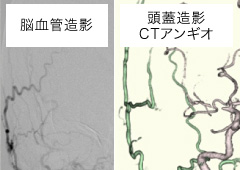

症例脳血行再建術(バイパス術)

手術前

手術前 手術後

手術後